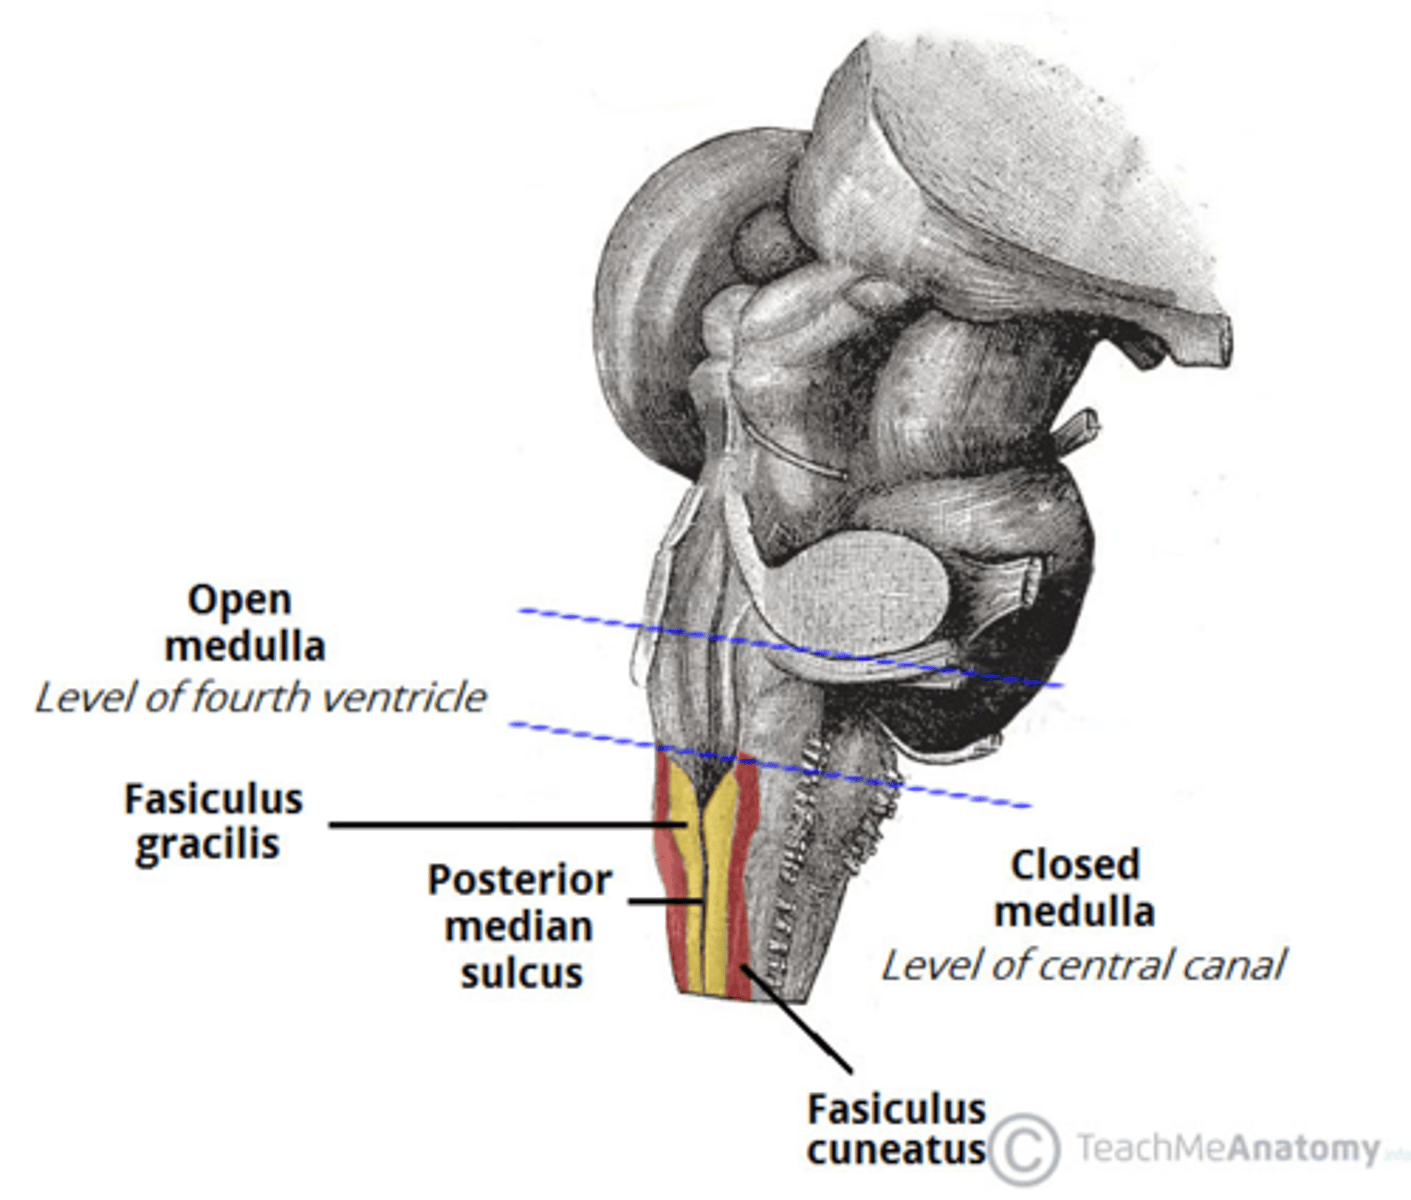

refers to the rostral portion of the medulla since there is no medullary tissue here on the dorsal aspect of the 4th ventricle

open

refers to the caudal portion of the medulla since there is medullary tissue here on the dorsal aspect of the 4th ventricle (therefore it is enveloped by the medulla)

closed

narrowed down portion of the 4th ventricle in the closed portion of the medulla

central canal

medial paired ridges of tissue on the dorsal aspect of the closed portion of the medulla

tractus gracilis

lateral paired ridges of tissue on the dorsal aspect of the closed portion of the medulla

tractus cuneatus

superior ends of the medial paired ridges of tissue on the dorsal aspect of the closed portion of the medulla, formed by namesake nuclei

gracilis tubercles

superior ends of the lateral paired ridges of tissue on the dorsal aspect of the closed portion of the medulla, formed by namesake nuclei

cuneatus tubercles

V-shaped boundary of the caudal aspect of the 4th ventricle that marks the boundary between the open and closed portions of the medulla

obex

name the groove

pontomedullary junction

general portion of the medulla

open medulla

general portion of the medulla

closed medulla

pyramids

ventral median fissure

pyramidal decussation

C

inferior cerebellar peduncles

cuneate tubercle

gracilis tubercle

cuneatus tract

gracilis tract

obex